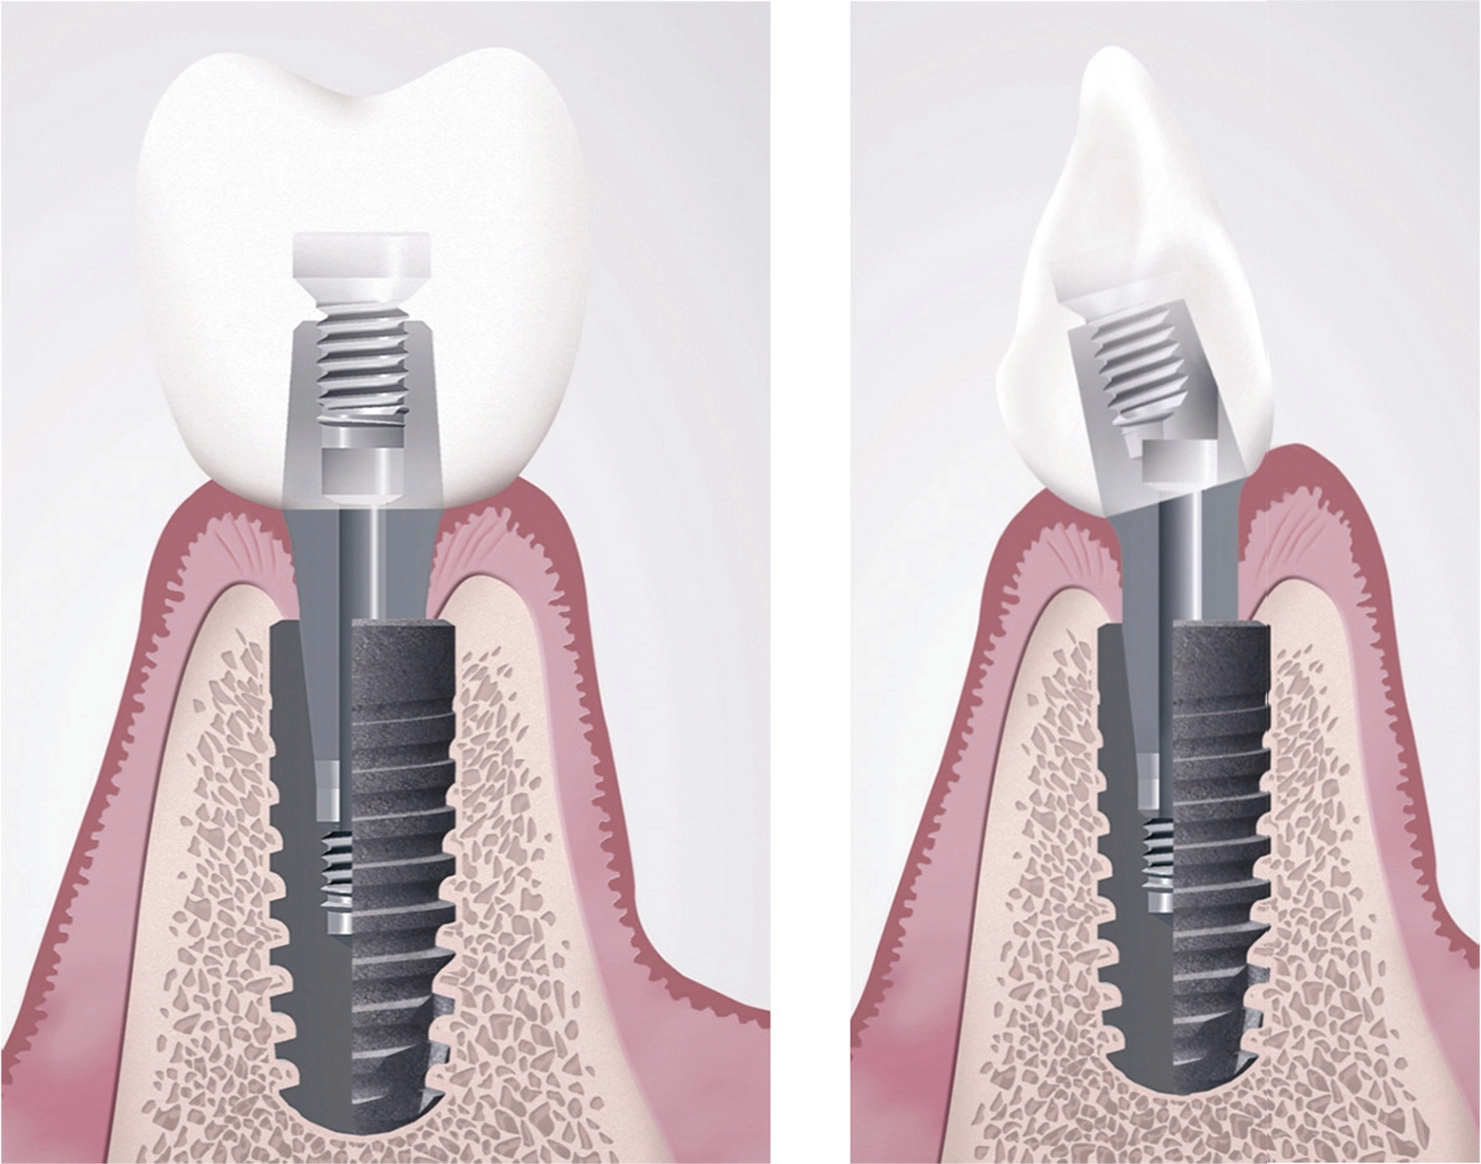

- Verschraubungen der Restauration mit dem Abutment

- Verschraubung der mit dem Abutment verklebten Restauration direkt im Implantat

- Verschraubung der Restauration mit dem Abutment

Eine immer mehr sich etablierende Alternative ist das sogenannte Kronenabutment, wo Abutment und Krone eine durch Klebung verbundene Einheit bilden und im Implantat verschraubt werden. Dies wird durch die sich laborseits immer mehr durchsetzende CAD/CAM-Technologie möglich und setzt voraus, dass die Konstruktionsdaten der betroffenen Implantatkomponenten (Basis- oder Standardabutments) durch die Hersteller hinterlegt und durch die Zahntechnik abgreifbar sind. Besonders vorteilhaft ist dieses Verfahren, wenn die Implantat-Abutmentverbindung konisch und bakteriendicht ausgeführt ist, da dann Schraubenlockerungen eine seltene Ausnahme darstellen.